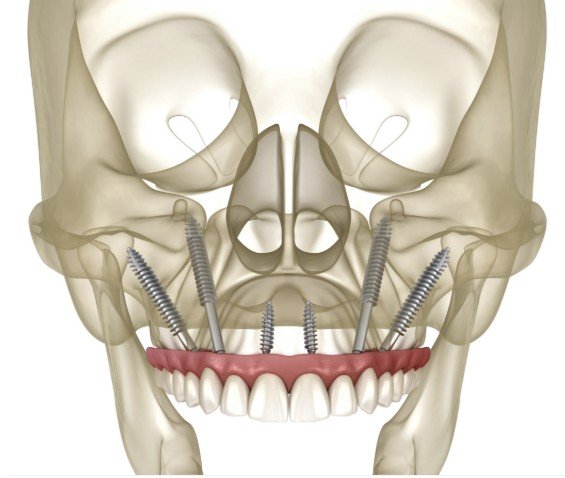

All-on-4 Dental Implants

The All-on-4 technique is designed for patients missing all or most of their upper or lower teeth. It involves placing four implants—two straight in the front and two angled in the back—to support a fixed bridge of up to 12 teeth. This method often eliminates the need for bone grafting, even in cases of bone loss, and allows the bridge to be attached within days of surgery for rapid restoration of function.

Full mouth dental implants are ideal for patients missing all or most of their upper and lower teeth who have sufficient bone density. This traditional approach uses up to eight implants per jaw to support a fixed bridge of up to 12 teeth. All implants are placed vertically in the upper and lower jawbone, providing a stable, long-term solution for those with adequate bone volume.

Zygomatic implants are a specialized option for patients with insufficient upper jaw (maxilla) bone density who wish to avoid procedures like bone grafting or sinus lifts. This technique involves placing longer implants (30–55mm) into the cheekbone (zygoma), which typically maintains strong bone mass. When performed by an experienced surgeon, zygomatic implants offer excellent outcomes for upper jaw restoration.